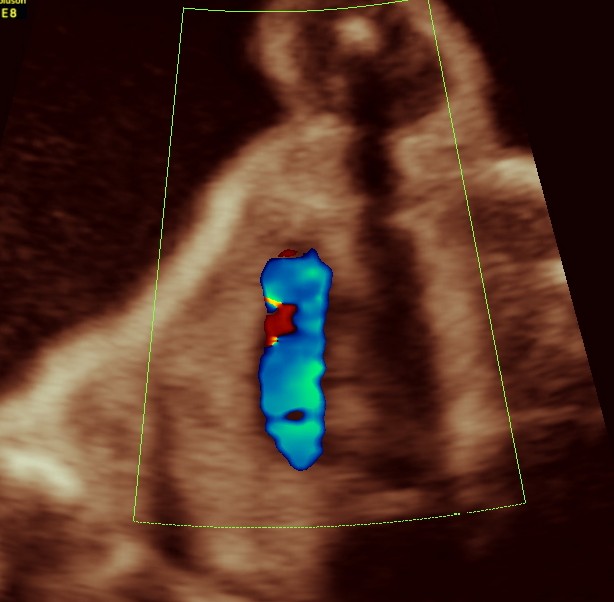

vsd is seen in the picture below.

generally colour flow imaging is not said to be very helpful